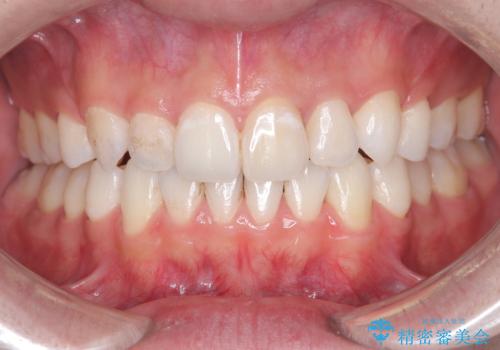

- 前歯が出ていることを主訴に来院されました。

臼歯関係が上顎前突傾向のため、上顎小臼歯を抜歯してインビザラインにて治療を行いました。

臼歯の咬合を作るために治療終盤ではゴムかけを行なっています。